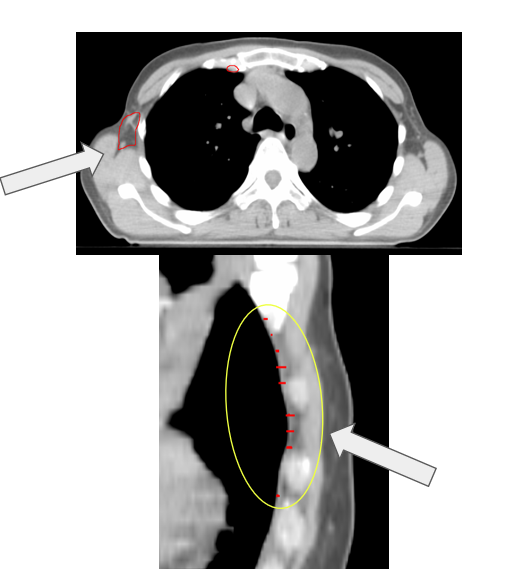

- Clinical IMN contours were inconsistent due to varying guidelines (RTOG vs ESTRO) and incomplete slices.

- Method A: Compared AI contours against clinical contours. This was unreliable due to inconsistent guidelines (RTOG vs ESTRO) and incomplete slices.

| Method B (AI-reviewed subset) | 32 | Z-length errors |

Clinical contours were too inconsistent to serve as a reliable ground-truth. The reviewed subset of Limbus contours was more effective for QA. The most common failure mode was incorrect Z-dimension contouring. Absolute length metrics introduced patient-size bias, making normalized ratios a better approach.